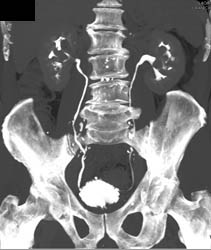

Diagnosis

Thickening of Bladder Wall